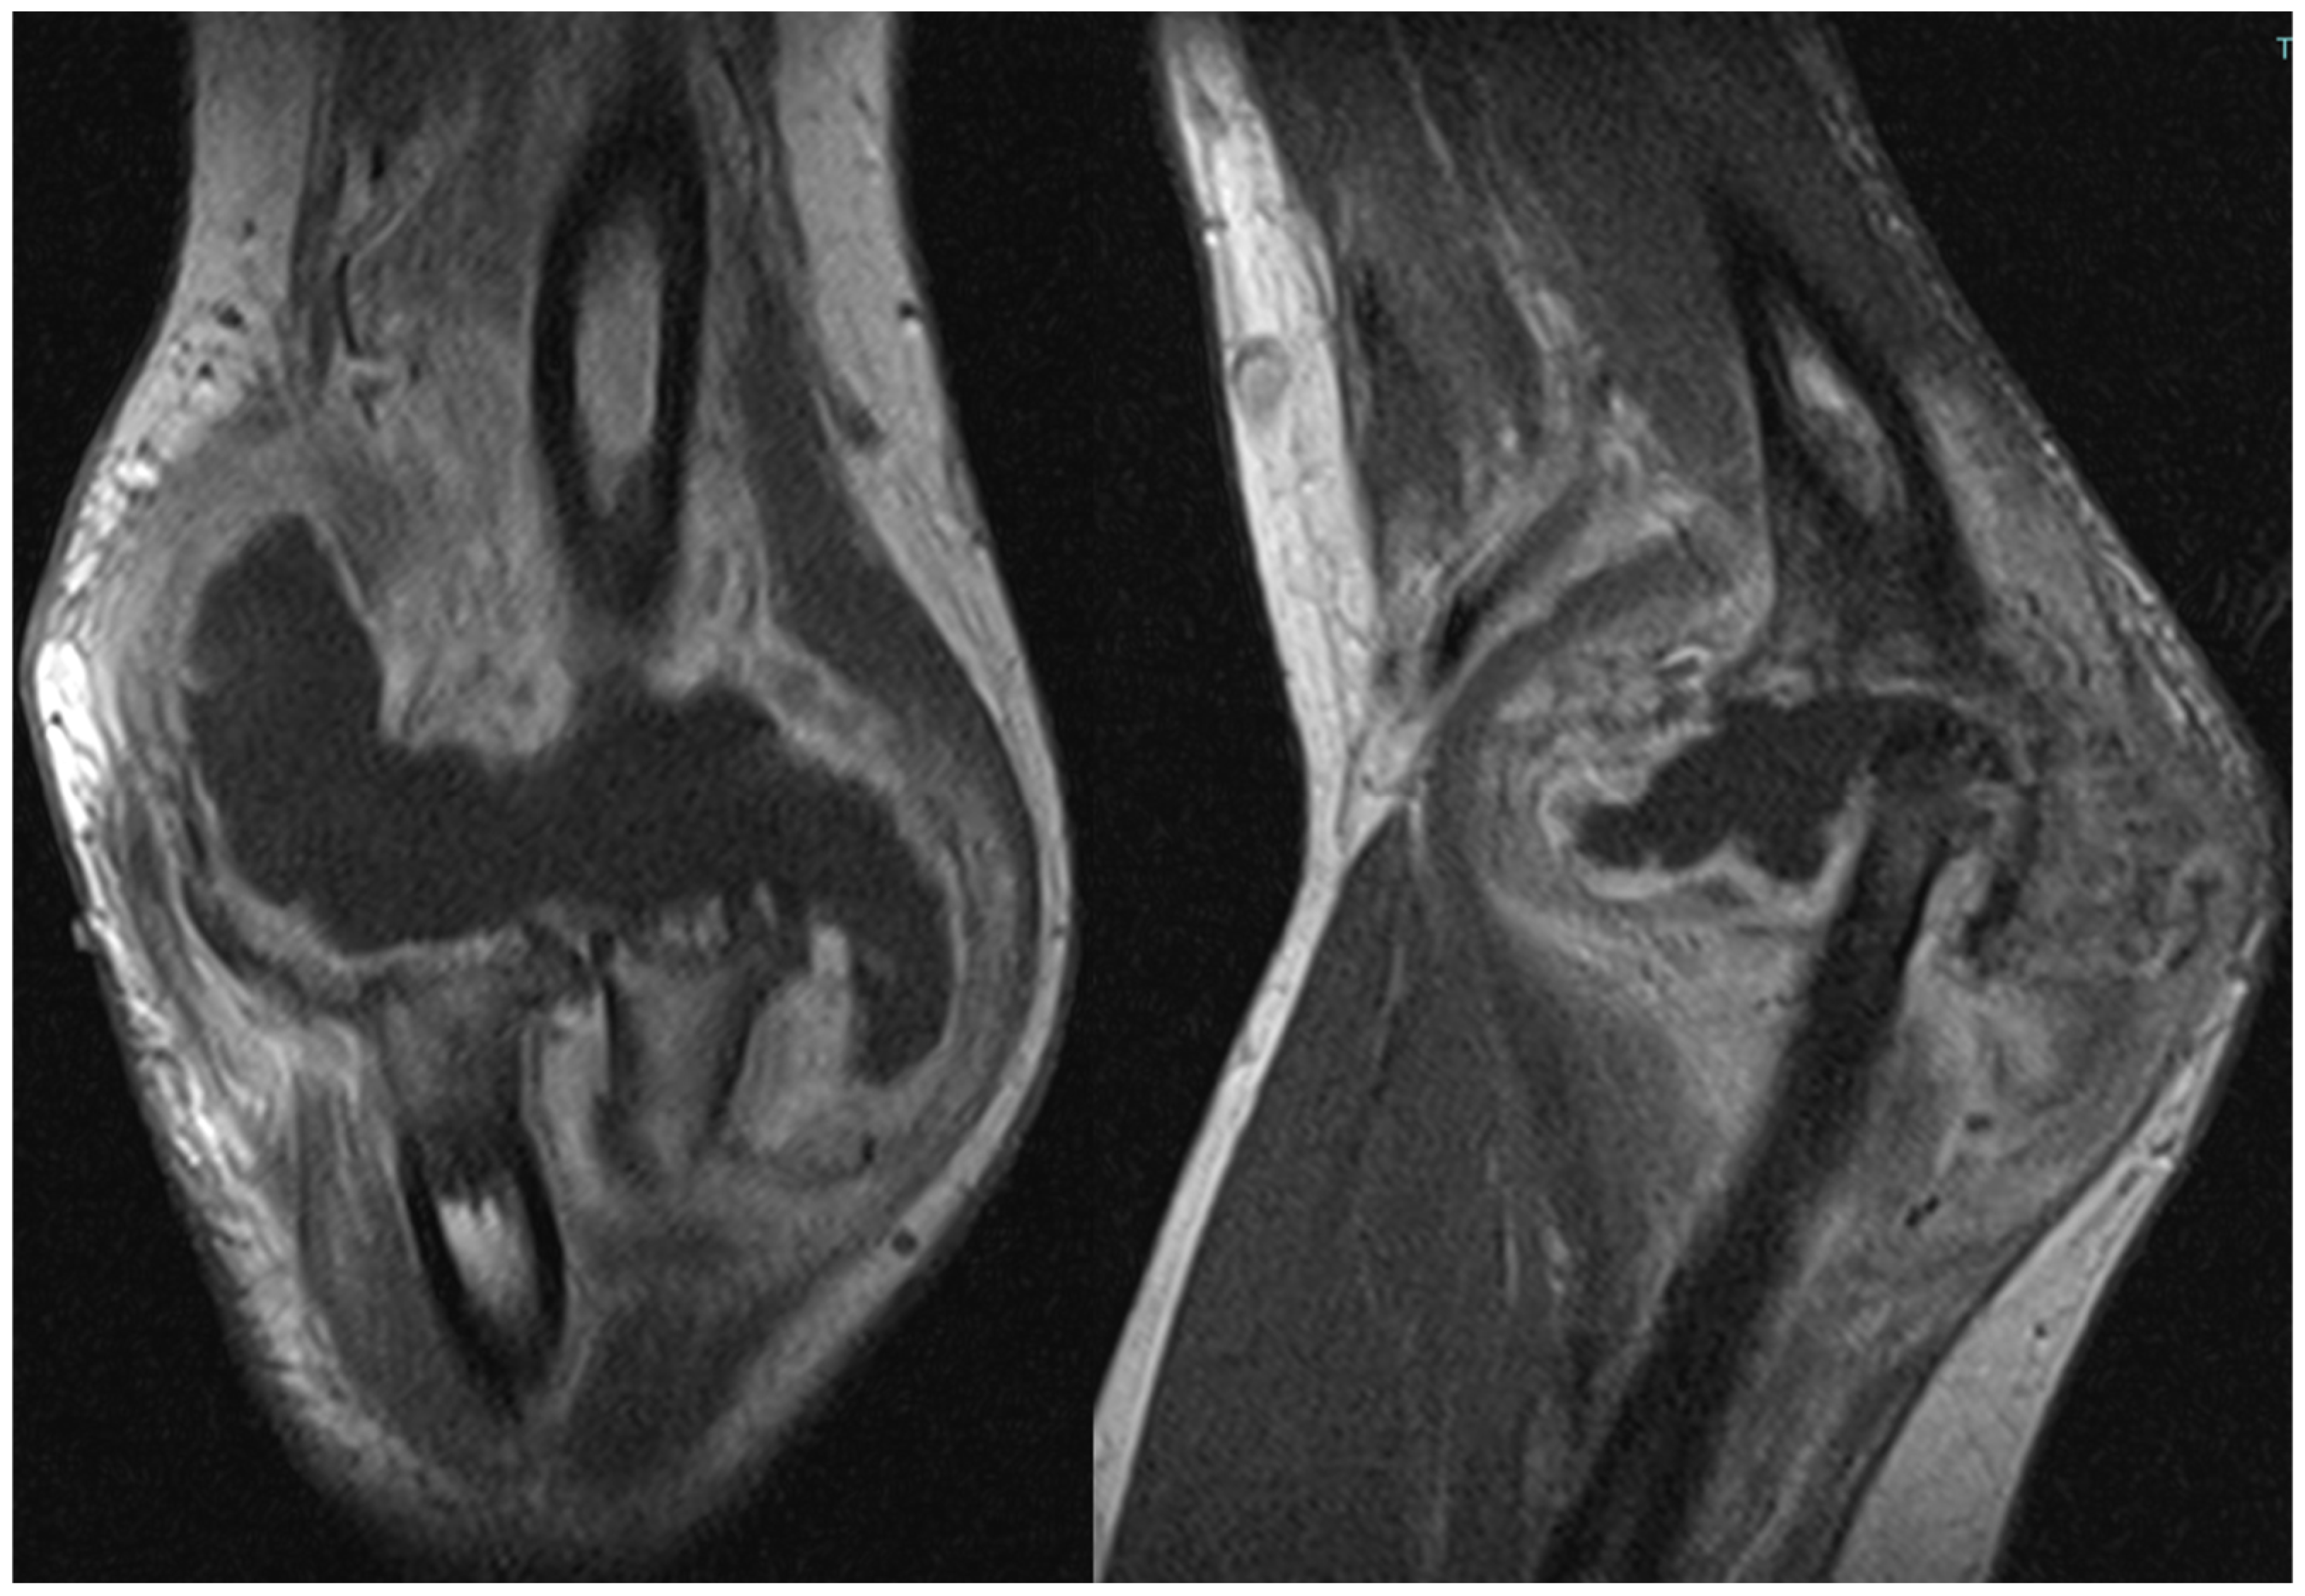

The patient also underwent magnetic resonance imaging (MRI) with and without contrast medium, which demonstrated subluxation between the articular surfaces of the elbow joint, edema and contrast enhancement in the spongy bone of the distal third of the humerus and proximal third of the radius, and a periosteal reaction at the humeral site without identifiable bone lesions, as shown in Figure 3. Additionally, the imaging revealed an abundant layer of joint effusion, with blood clots and loose bodies, at the joint level. The synovium appeared thickened and full of contrast enhancement, and the periarticular soft tissues also displayed thickening with edema and soft contrasting infiltration on the proximal ulnar side. In light of the known basic arthropathy and the patient’s clinical presentation, these radiological findings suggested an arthritic arthro-synovitis picture with soft tissue involvement, without excluding an infectious nature, rather than osteomyelitis, as there was no cavity of necrotic bone with fistula and bone marrow inflammation.

Figure 3.

Magnetic resonance imaging (MRI) coronal and sagittal T1 weight views of the right elbow. Involvement of periarticular soft tissue with a large mass through the articulation.

MRI is considered the most sensitive test for arthropathy and remains more sensitive than other imaging modalities, despite being less sensitive in the elbow compared to other joints. Evaluations should include coronal, sagittal, and axial examinations. Cross et al. recommend a T1 sequence for osteochondral lesions, with unenhanced gradient echo best for viewing synovium, cartilage, and hemosiderin deposition. T2 gradient echo is effective for identifying acute and chronic bleeding and distinguishing between simple effusion and hemorrhage [28].

MRI can identify even minor changes in the affected joint, significantly impacting patient management [30]. Several MRI-based rating scales for HA have been suggested [31,32,33,34]. The revised 2005 International Prophylaxis Study Group (IPSG) scale, based on the IPSG MRI scale, uses a single scoring system to include soft tissue changes like effusion and hemarthrosis, distinguishing between soft tissue and osteochondral changes to better reflect disease progression [28]. Computed tomography (CT) focuses on the primary structures and modifications of bones [35]. Both CT and MRI can determine the extent of hemophilic pseudotumors, which are chronic, encapsulated hemorrhagic fluid collections that typically destroy bone and can grow significantly [30]. Three-dimensional (3D) CT aids in surgical planning for total elbow arthroplasty (TEA), helping estimate implant size and placement [36]. Angiography with arterial embolization, despite being invasive and carrying some risk, reveals vascular blush, false aneurysms, true aneurysms, and arteriovenous shunts causing bleeding. Although spontaneous periarticular aneurysms causing hemarthrosis are rare, angiographic embolization offers a promising, coagulation factor-saving treatment for joint bleeds unresponsive to replacement therapy.